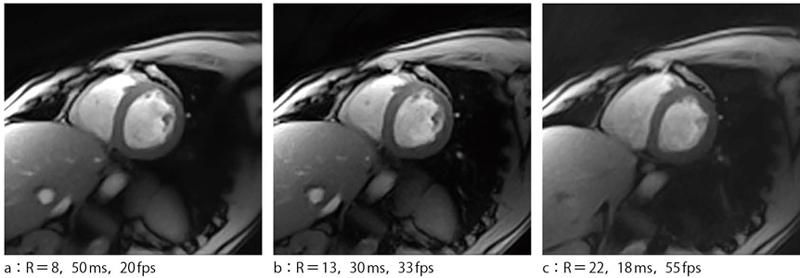

Compressed Sensingの数学的な理論は,2006年にCandes,Donohoらにより発表されている3),4)。本法はSparse(疎)なデータサンプリングから解(画像)を求める手法である。通常,求める変数以上のサンプル数がなければ解は求まらないが,Compressed Sensingでは,解が疎である,求める画像に境界(大きく数値が変化する場所)が少ない,などの仮定をもとに,l1 Norm最小値化法という数学的手法を用いて逐次的に画像を再構成する。現在MRで用いられている画像再構成法では,一般にデータ量が減ると空間分解能が低下してしまうが,本法ではコントラストが高い場合,空間分解能が十分に維持されるという特徴があり,コントラスト分解能が高いMRIに適合した方法と言える。さらに受信,送信系のハードの追加なしに,数十といったReduction Factorを得ることができ,CINE撮像では20msという時間分解能も得ることができている5)図3)。これは50fpsに相当し,血管撮像装置にも引けをとらない時間分解能である。ただし,現状,計算時間が膨大となるため,再構成システムの開発や新しいアルゴリズムの開発が行われている。

図3 Compressed SensingによるCINE画像 (R:Reduction Factor)

(R:Reduction Factor)